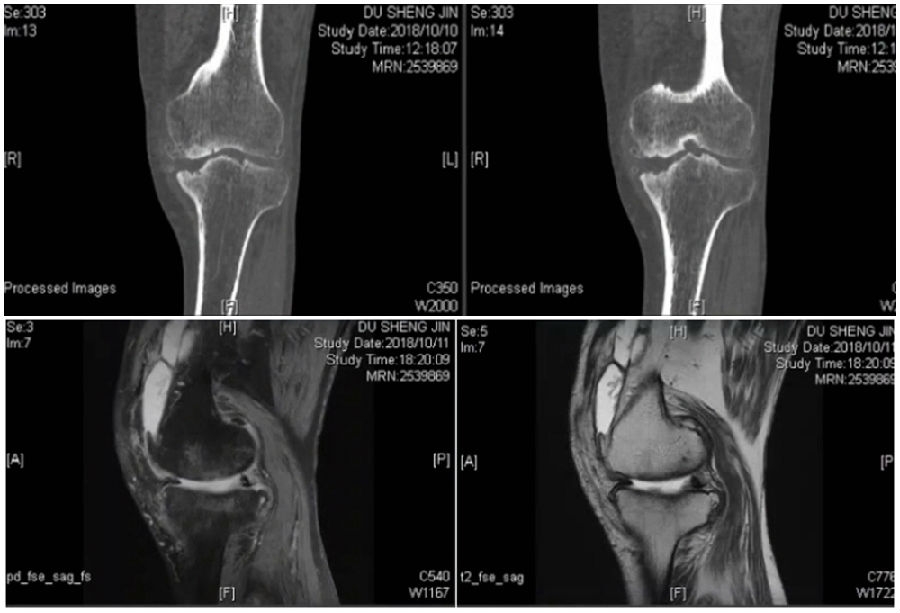

术前

术前影像资料

术前MRI

术前规划:

①关节内截骨,内外侧平台平行。

关节内截骨

②再次确定下肢力线。

确定力线

③关节外截骨。

关节外截骨

④术中首先关节镜探查。关节镜下软骨损伤3度,软骨脱落,软骨下骨暴露。

关节镜下所示